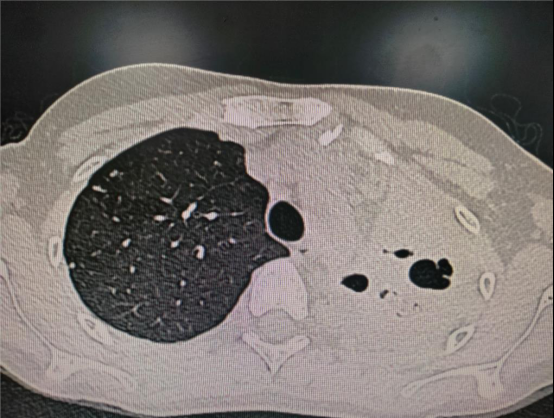

右侧膈肌破裂2.右下肺压迫性肺不张.

1月19日,患者被犁地机"犁"伤胸部致开放性血气胸,肺裂伤肺内血肿形成